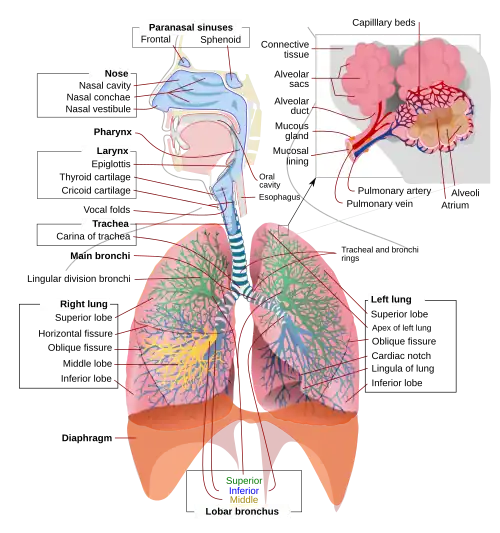

Åndedrætssystemet eller respirationssystemet udgøres af de organer, som bruges til at trække vejret med. De består af næsen, svælget, luftrøret, bronkierne og lungerne. I næsen opvarmes og fugtes luften før den kommer ned i lungerne.

Luftrøret og bronkierne leder luften ned til lungerne. Slimhinderne i luftrør og bronkier er beklædt med små fimrehår som kaldes cilier, de fjerner indåndede støvpartikler o.l. Lungerne er placeret i brysthulen og er omgivet af to hinder med væske imellem. Den yderst af de to hinder sidder fast på lungernes overflade. De mindste bronkiegrene, bronkiolerne, ender i små blærer, de såkaldte alveoler. Herved opnår lungerne en meget stor indre overflade.

I lungerne optages den ilt som mitokondrierne skal bruge til at lave respiration med og afgivelsen af det kuldioxid som bliver dannet ved respirationen. Transporten af disse stoffer sker ved diffusion til og fra de små blodkar, der slutter sammen alveolerne og kan lade sig gøre, fordi lungerne har en så stor indre overflade ( ca. 100 kvadratmeter hos mennesker ).